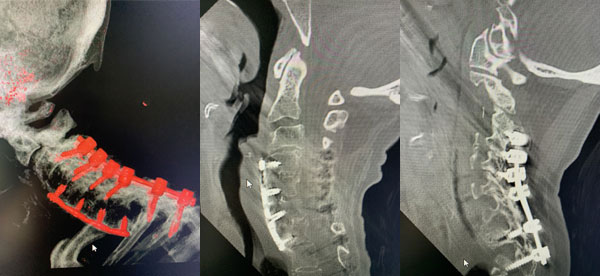

Figures 2a, b, c: Preoperative sagittal CT scans of the cervical spine demonstrating preoperative instrumentation. Note degenerative changes and anteriolisthesis of C2 and C3.